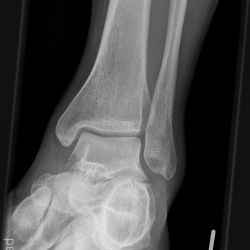

Snowboard fracture Talus